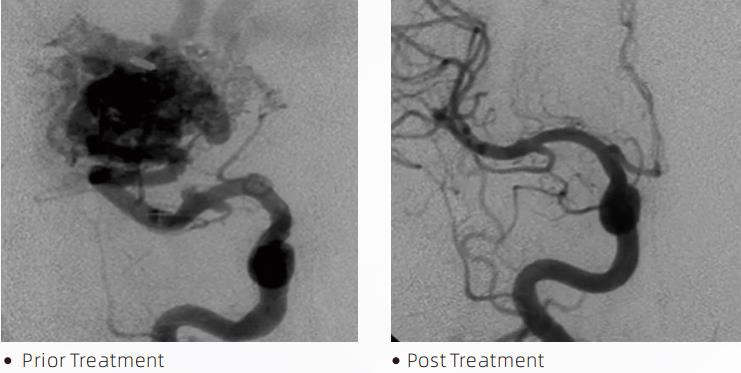

Lav lajidoLiquid Embolic System se yon terapi endovaskilè entèvansyon pou tretman malformasyon serebral. Malformation serebrovaskilè refere a yon gwoup anomali nerovaskilè benign oswa malfezan ki ka mennen nan emoraji entrakranyen, enfaktis serebral, iskemi serebral ak lòt maladi. Sistèm embolizasyon likid la se yon aparèy medikal ki administre atravè ensèsyon entravaskilè senp, ki anbolize veso sangen serebral nòmal pa enjekte yon materyèl likid espesyal. Materyèl likid la fòme yon anbolis tisi kontwole nan veso sangen yo, ki ka diminye enpak malformasyon serebwo vaskilè sou pasyan yo. Yo itilize yon mikwo katetè livrezon konpatib DMSO ki endike pou itilize nan neurovasculature a pou jwenn aksè nan sit anbòl la. Ajan anbolik likid lav se yon sistèm ajan anbolik likid ki pa adezif ki gen ladann copolymer EVOH (etilèn vinil alkòl) ki fonn nan DMSO (dimethyl sulfoxide), ak sispann poud tantal mikronize pou bay kontras pou vizyalizasyon anba fluoroskopi. LavTMdisponib nan twa fòmilasyon pwodwi, LAVA-12, LAVA-18 ak LAVA-34. LAVA-12: Rekòmande lè w ap manje mikwo veso distal yo ak nan ti manje yo. LAVA-18: Rekòmande lè yo pral bay piki pedikil yo tou pre nidus la; LAVA-34: Rekòmande pou anbolize pi wo koule ak pi gwo konpozan fistulous.